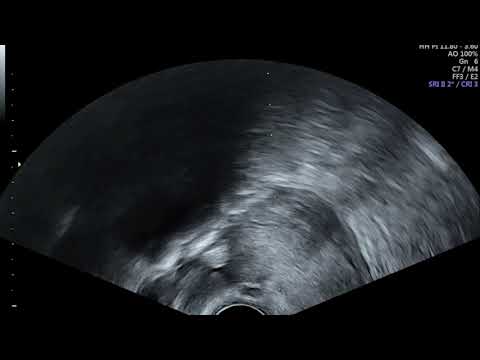

Hellow guys, Welcome to my website, and you are watching LAPAROSCOPIC SCLEROTHERAPY FOR AN ENDOMETRIOMA IN 10 STEPS. and this vIdeo is uploaded by Fertility & Sterility at 2022-03-29T15:42:22-07:00. We are pramote this video only for entertainment and educational perpose only. So, I hop you like our website.